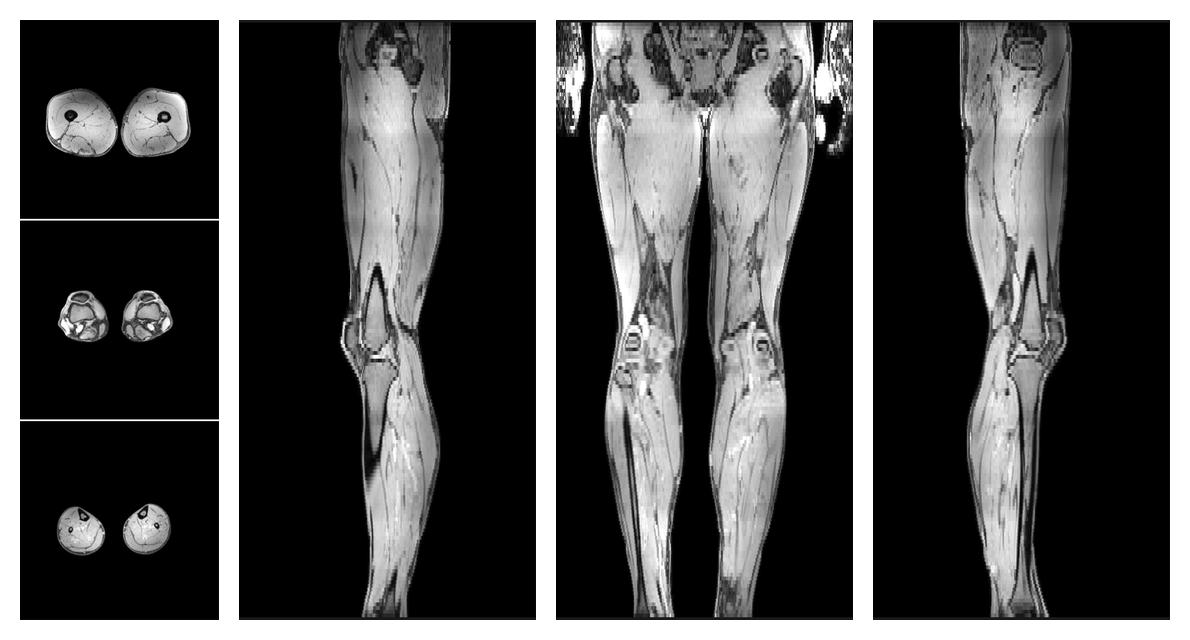

Water only T2 mapping

Multi echo spin echo T2 relaxation time mapping with EPG reconstruction, for information look here».

• Water only signal

The water part of the acquired multi-echo spin echo data.